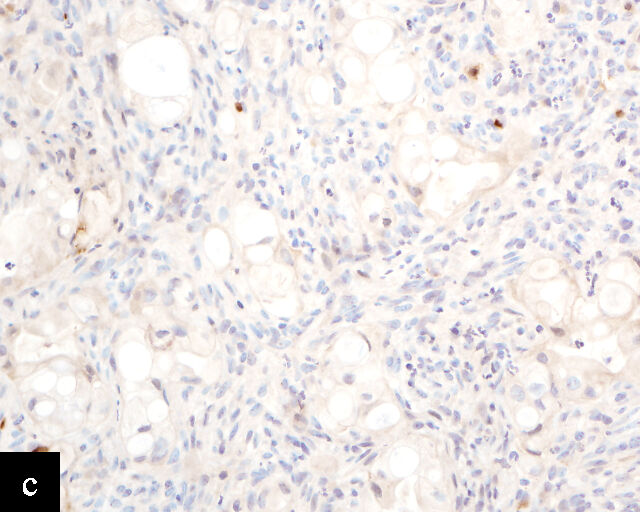

3

Immunohistochemical profile of HPV-independent cervical carcinomas. (a,b) Clear cell adenocarcinoma. (c,d) Gastric-type adenocarcinoma. HPV-independent cervical carcinomas do not show p16 diffuse expression (a,c) and are PAX8 positive (b,d). Magnification ×20.

Clear cell adenocarcinomas of the cervix follow a bimodal age distribution. The first peak is observed at late adolescence/early adulthood13,14 and is associated with in-utero exposure to diethylstilbestrol (DES). The median age at presentation for clear cell adenocarcinoma not related to DES exposure is 48 years15 and constitutes the second peak. Its histological appearance resembles that of clear cell adenocarcinomas from other parts of the female genital tract (uterine corpus and ovaries), in particular tumor cells displaying overt nuclear atypia and a characteristic clear cytoplasm, arranged in variable destructive growth patterns16 (Figure 2a). Clear cell adenocarcinomas of the cervix share common immunophenotypic features with upper female genital tract carcinomas, notably PAX8 positivity and non-diffuse p16 expression17 (Figure 3a,b). Limited data from case series indicate that mutations in CMTM5 and WWTR1 are relatively frequently detected in clear cell adenocarcinomas of the cervix.18,19

Gastric-type adenocarcinoma of the cervix produces neutral mucin and is termed ‘gastric-type’ because neutral mucin is commonly found in gastric adenocarcinomas.27 Its phenotypic resemblance to gastric adenocarcinoma can also be seen in its clear-to-pale eosinophilic, abundant cytoplasm28 and expression of HIK1083 (gastric O-glycan),29 MUC6 (gastric mucin)30 and TFF2 (gastric mucosal peptide).31 As compared to other HPV-independent adenocarcinomas, PAX8 expression is variable in gastric-type adenocarcinomas32 (Figure 3c,d). Mutations in TP53, CDKN2A, KRAS, ERBB2 and ERBB3 (≥10%)33,34 are found in gastric-type adenocarcinomas.